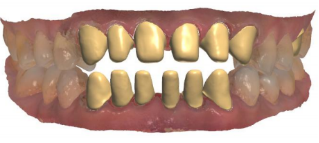

修复前的牙齿

修复后的牙齿

Cad软件预先设计排牙 设定内冠锆边 准备回切

内冠回切并最终设计完成